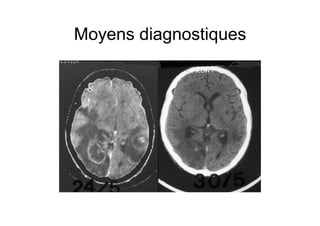

Moyens diagnostiques

•  Scanner cérébral sans et avec injection

Abcès prenant le contraste en anneau

associés à un œdème périlésionnel,

souvent multiples

Apport important de l’IRM

•  Sérologie toxoplasmose positive en Ig G

•  Efficacité du traitement présomptif au bout

de 14 jours